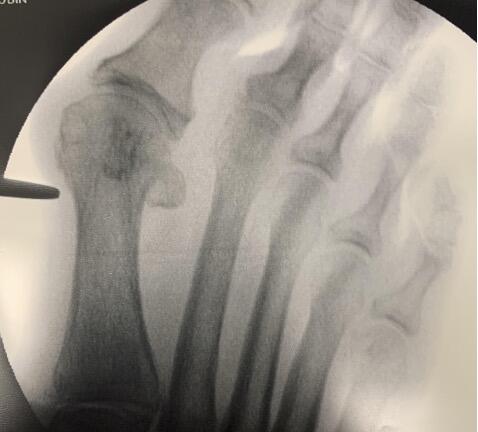

Incision Placement. Confirmation of the incision site via intraoperative fluoroscopy can ensure placement directly medial to the metatarsal, just proximal to the flare of the metatarsal head, with care taken to avoid the sesamoid apparatus/articulation (see first photo above). In our experience, the medial first metatarsal incision must be at the midline of the bone. Initially, it may prove beneficial to orient the incision horizontally, in line with the metatarsal, in case one elects to convert to an open approach. A horizontal incision also poses less of a risk of iatrogenic damage to the neurovasculature.

The surgeon can then confirm the trajectory and depth of the burr with fluoroscopy. In our experience and from what we have learned, the initial pass of the burr should be a direct drill hole, straight through the medial and lateral cortex of the first metatarsal neck (see second photo above). The entry point of the burr within the medial cortex should remain static for the entirety of the osteotomy. The remainder of the osteotomy then takes place around this pivot point. The hand should rotate plantarly for the dorsal portion of the osteotomy, perpendicular to the long axis of the metatarsal. Conversely, the hand will rotate dorsally to complete the osteotomy through the plantar cortex. Methods may vary, such as a “poke and drag” technique or working in quadrants.